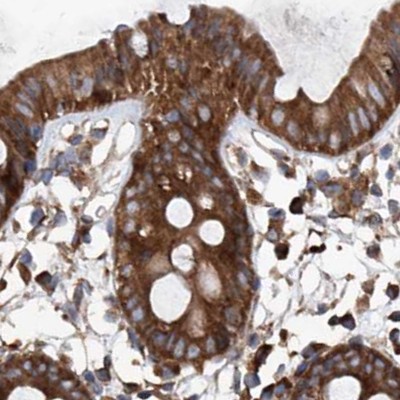

Immunohistochemical staining of human cerebral cortex, colon, lymph node and testis using Anti-ASCC3 antibody HPA031610 (A) shows similar protein distribution across tissues to independent antibody HPA031608 (B).